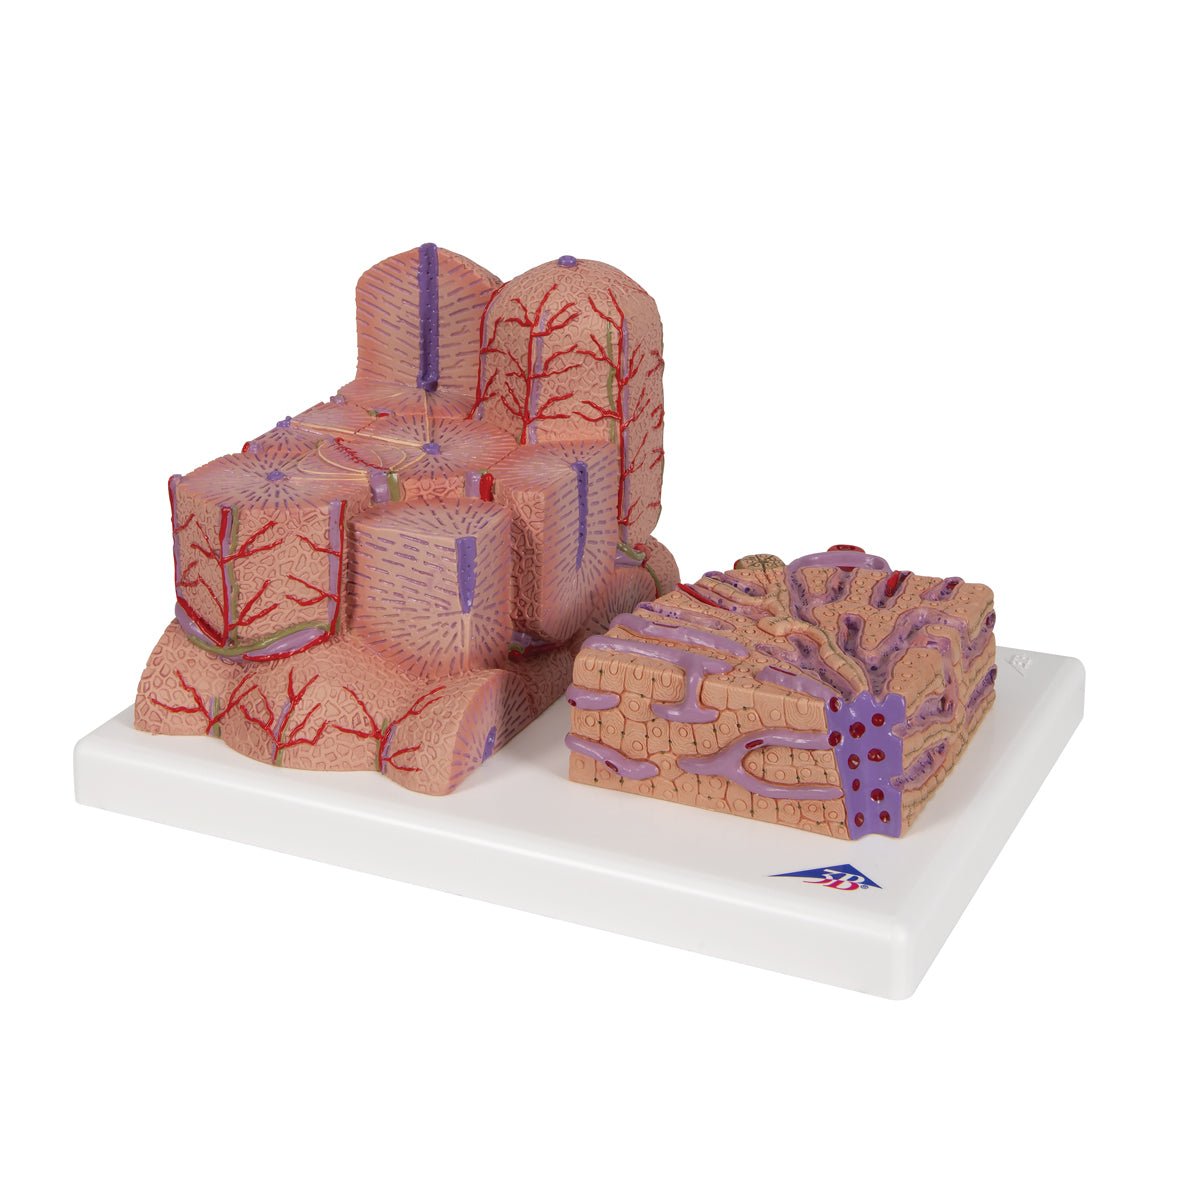

Salg af anatomiske modeller er det bærende element i eAnatomi, selvom vi også bruger mange ressourcer på at udvikle vores egne anatomiske materialer som fx plakater. Anatomiske modeller anvendes til forskellige formål og kan både vise afgrænset væv, organer samt organsystemer. Søger du en simpel model af knoglevæv eller måske en avanceret torso-model baseret på MRI teknologi, kan du finde det hele på eanatomi.com.